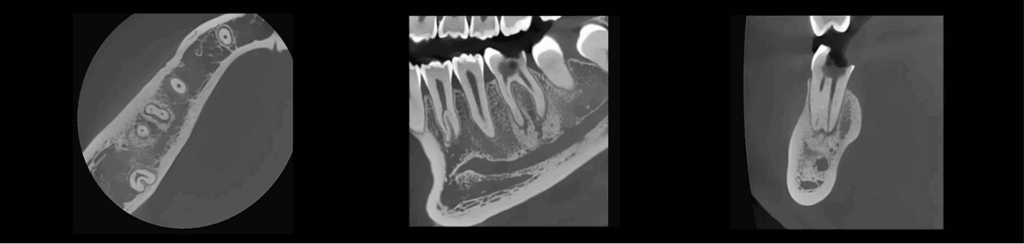

5 x 5 cm

9 x 9 cm

12 x 10 cm

OPTIONS EXCLUSIVES DE CHAMP DE VISION DU RUBIK X3

16 x 11 cm

18 x 13 cm

18 x 20 cm